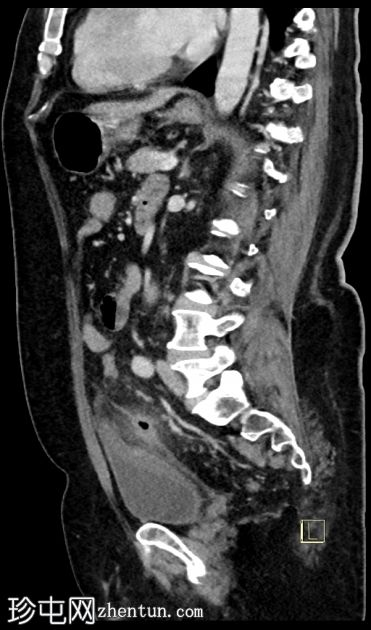

矢状位增强扫描(门静脉期)

6.jpg

先前观察到的乙状结肠壁增厚和结肠周围脂肪间隙模糊进展,并新发现左侧结肠周围小软组织密度影(蜂窝织炎),大小为3.0 x 2.0 cm,可见中央气腔。该蜂窝织炎位于先前观察到的左侧壁缺损附近。

膀胱顶部反应性壁增厚。

未见气腹、腹水或腹腔内脓肿。

该病例表现出复杂性急性乙状结肠憩室炎的典型特征,伴有乙状结肠局部穿孔,提示为1A期复杂性急性憩室炎。患者接受了广谱抗生素保守治疗,1个月后因临床症状加重前来复诊。复查CT显示乙状结肠憩室炎恶化,出现结肠周围小蜂窝织炎,内含少量气腔。但未见弥漫性腹膜炎的征象,如腹水、气腹或弥漫性腹膜/大网膜混浊。之后患者失访。